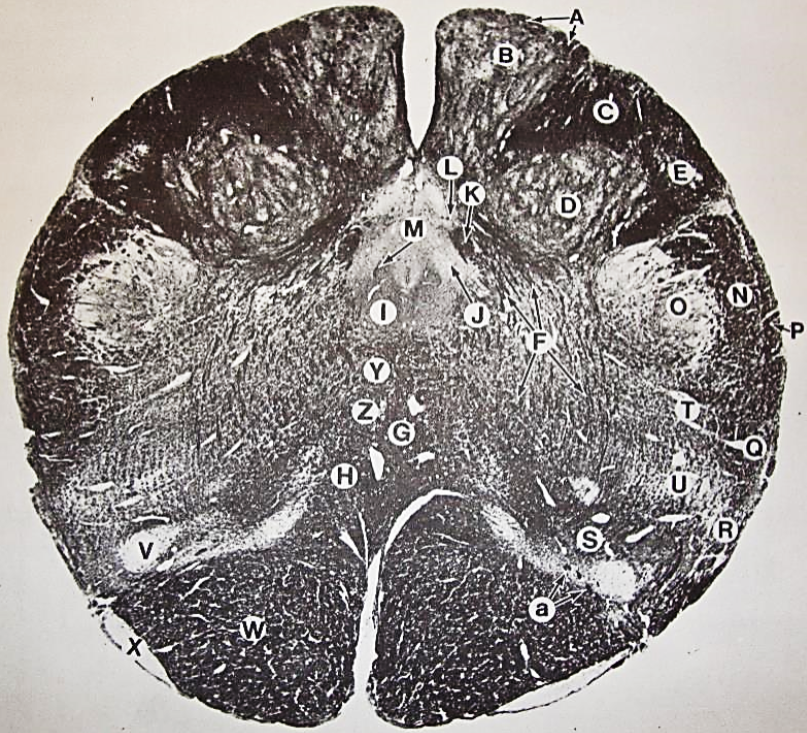

A

posterior median sulcus

B

posterior intermediate sulcus

C

anterior median fissure

D

gracile fasciculus

E

Gracile nucleus

F

fasciculus cuneatus

G

spinal trigeminal tract

H+I collectively

spinal trigeminal nucleus

J

Accessory nucleus

K

pyramidal decussation

L

lateral corticospinal tract

M

rubrospinal tract

N

posterior spinocerebellar tract

O

anterior spinocerebellar tract

P

lateral spinothalamic tract

Q

anterior spinothalamic tract

R

lateral vestibulospinal tract

S

medial longitudinal fasciculus

T

tectospinal tract

U

central canal